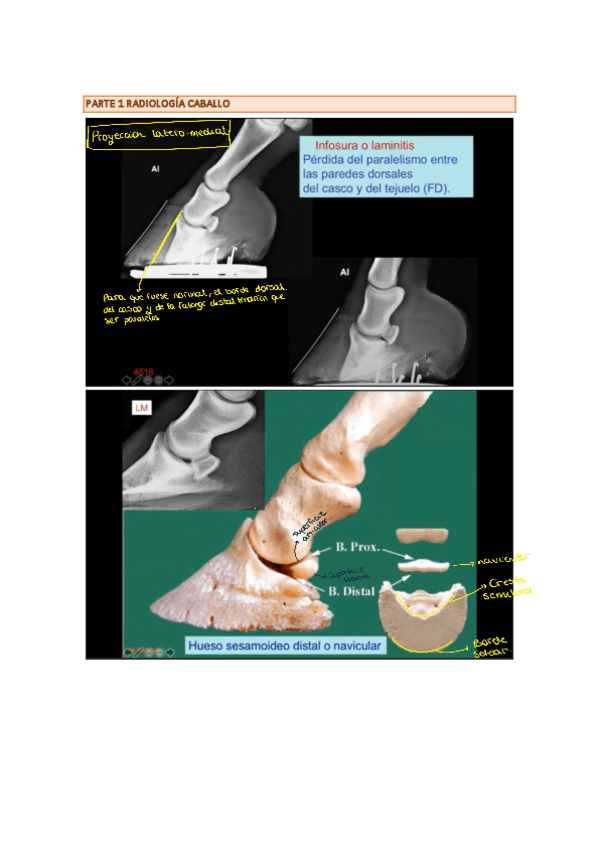

Imágenes de radiografias explicadas

He publicado nuevos apuntes de 3º Diagnóstico Por la Imagen: Imágenes de radiografias explicadas

Rx-equina-1.pdf